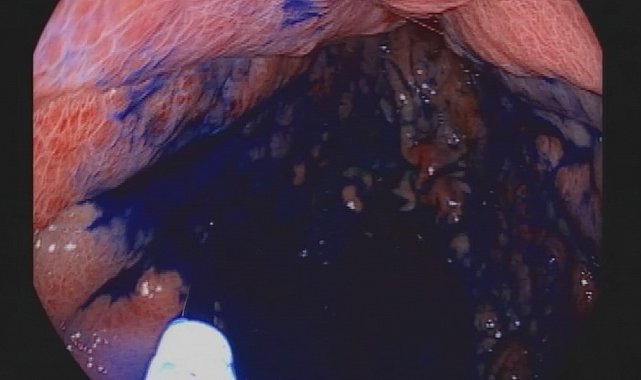

"Biz endoskopi yaparken, hem gastroskopi hem kolonoskopi yapıyoruz. Mide ve kalın bağırsak mukozasını özel boyalarla boyuyoruz. Bu işlem, normal mukoza ile kanserli hücre arasındaki farkı belirgin hale getiriyor. Çünkü endoskopide temel olan cerrahın ya da endoskopi yapan endoskopistin mukozayı çok iyi araştırması, ayrıntılı muayene etmesi, farklı olan bölgeleri yakalaması ve oradan biyopsi almasıdır. Ancak normal ışıklı endoskopilerle bunu yakalamak her zaman mümkün olmuyor. Bunu ancak kromoendoskopi dediğimiz boyama tekniği ile yakalamak mümkün hale geliyor. Endoskopik işlem sırasında boyayla mukozayı boyuyoruz. Burada kanserli ya da kanser öncesi hücreler, verdiğimiz bu boyayı az yakalıyor. Ardından aynı mukozayı yıkayıp tekrar bakıyoruz fakat bu tür kanserli hücreler yakalamış olduğu boyayı bırakmıyor. Mukoza eski pembe kırmızı halini alırken kanser hücreleri az da olsa tutmuş olduğu boyayı bırakmıyor. Bu farklı noktalardan biyopsi alıyoruz ve hastalığı erken yakalıyoruz."